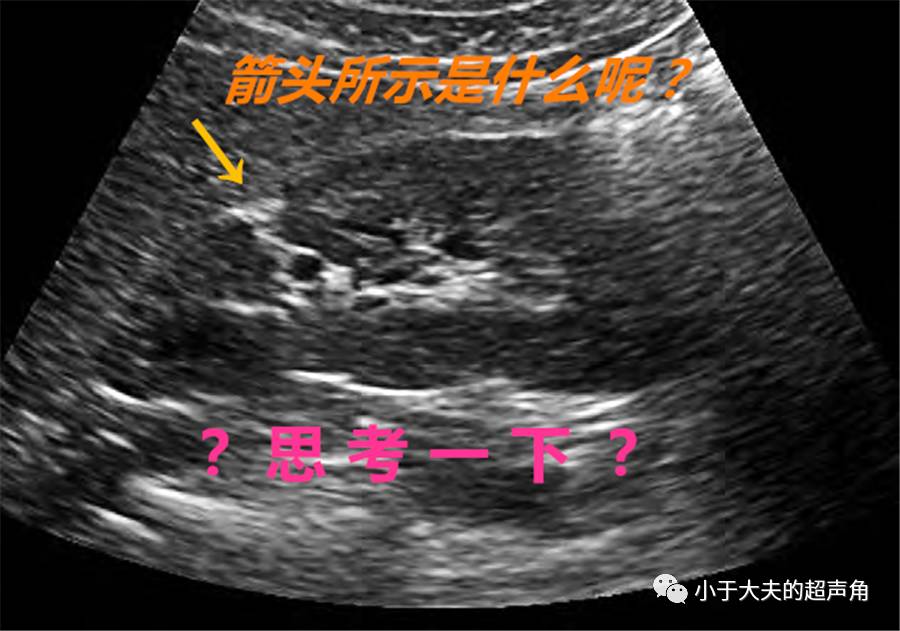

图1:肾脏实质内线样高回声,会是什么呢?

图中箭头所示线样高回声为肾脏连接部实质缺损(Junctional parenchymal defect, JPD)。JPD也可为三角形,尖朝向肾窦。

注意JPD高回声,向外上方与肾周脂肪囊相延续,同时,向内下方与肾窦相延续。